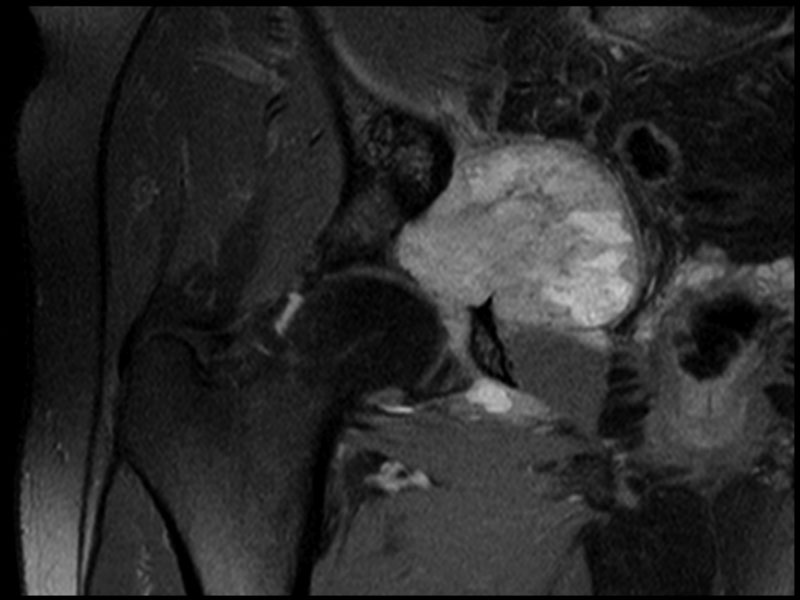

Fig 2. Coronal MRI showing acetabular tumour